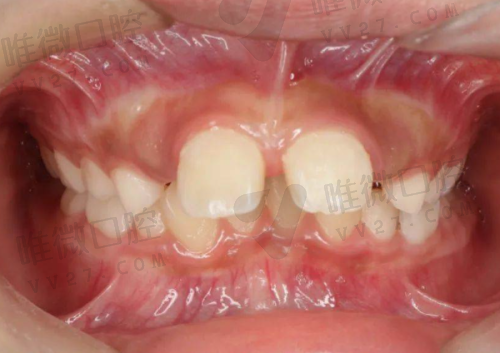

「预算有限选韩国登腾,成效绝了!」——小李,29岁,大门牙掉了一颗,怕影响容貌。选了韩国登腾Super Line+全瓷冠,总共花了9500元。种完之后,同事都没看出来是假牙:“摩尔的医生技术好,伤口小,我周五种的,周一就去上班了,完全没影响!”